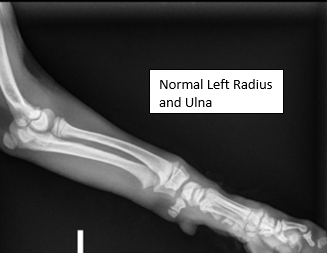

Diagnosis: Radial hemimelia (radial and carpal aplasia)

Assessment: Windsor initially presented to Pawsitive Steps Rehabilitation and Sports Medicine for evaluation of a congenital right forelimb deformity, where a portion of his right radius did not develop. At the time of initial presentation, Windsor was still growing, so a permanent device to correct the deformity was not recommended. Windsor was placed in a temporary splint and bandage until his growth plates solidified. He was then fitted for an orthotic/prosthetic device which allows him to properly posture and bear weight, realigning his anatomy to optimal positioning. Over the past couple of months, Windsor has been acclimating well to device, demonstrating solid mobility and stability. Windsor has also gained muscle mass in his right front limb and has strengthened his core and hindlimb musculature.